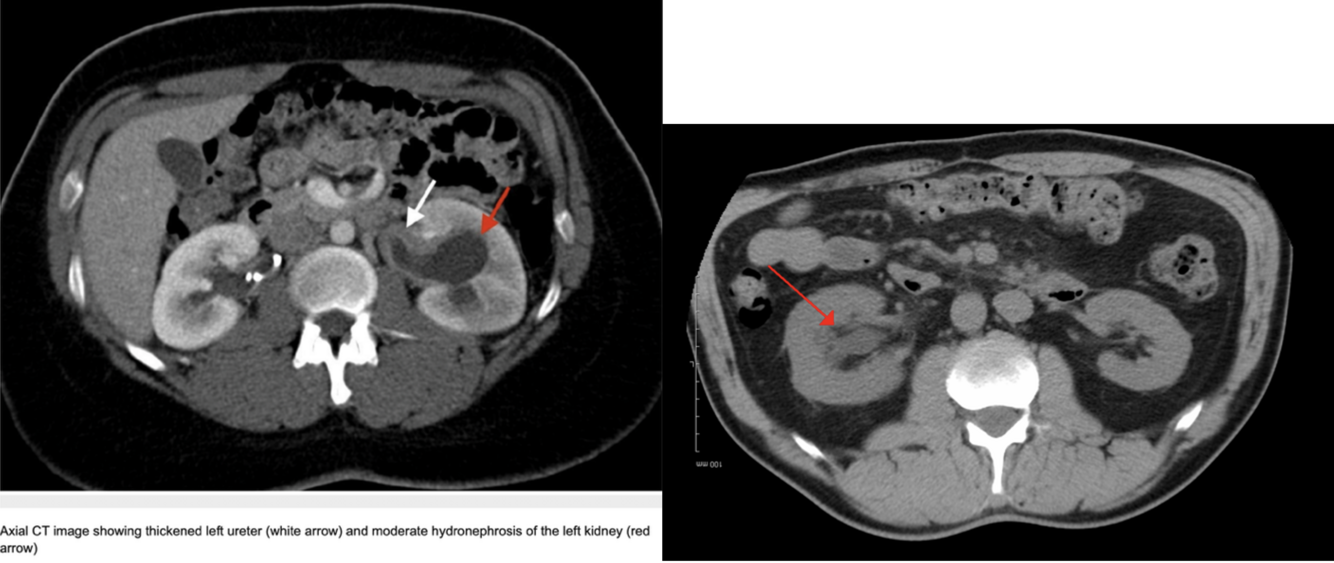

Hydronefrose:

18

Q

Diagnose?

19